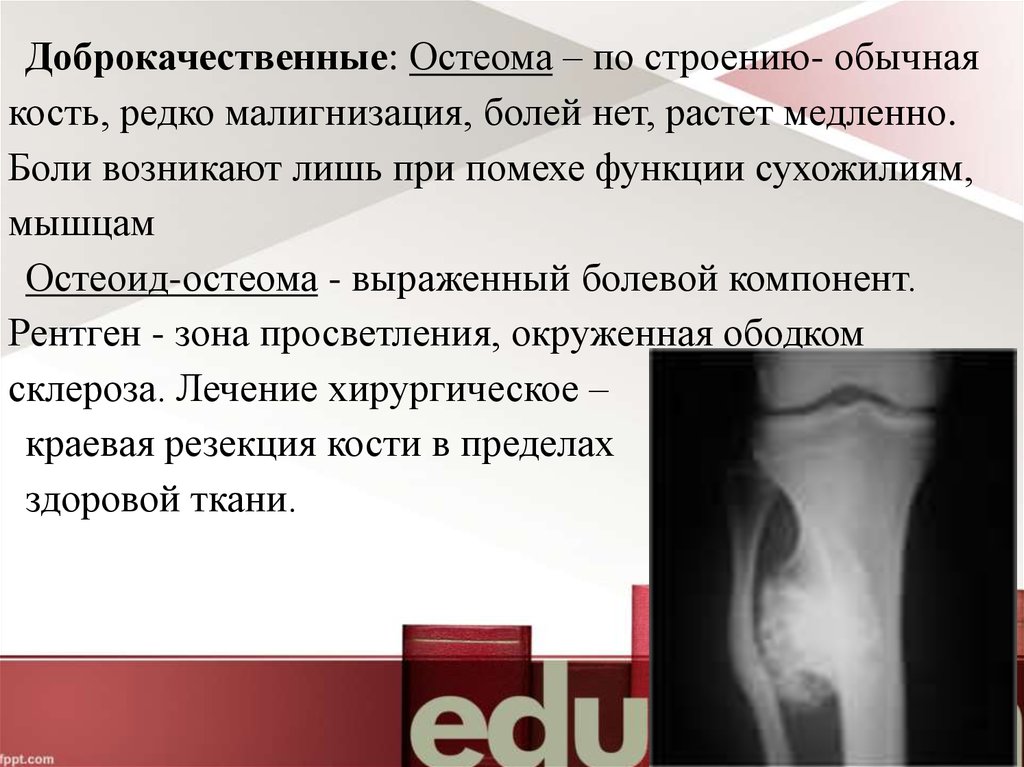

Первичные костные опухоли.

Рассмотрите возможность хирургического удаления остеомы, особенно если она вызывает боль или ограничивает движение.

Остеома

Обсудите с врачом возможность использования медикаментозного лечения для уменьшения симптомов остеомы.

Принимайте противовоспалительные препараты по назначению врача для снижения воспаления и боли.